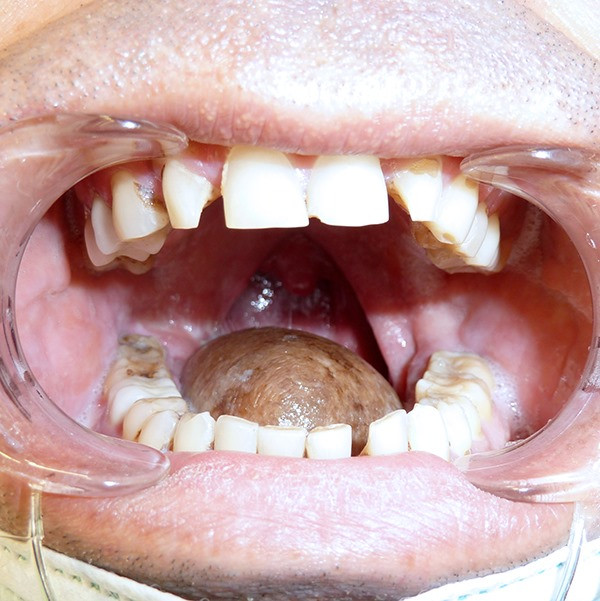

The patient is 50-year-old male who had been diagnosed with advanced tongue cancer. The entire tongue was removed together with the tumor, afterwards the doctors managed to store the tongue completely with a patch of dermal and muscular tissue which were obtained from the lateral surface of the chest and provided with blood vessels and nerves.

The uniqueness of this surgery, which has been performed in Armenia for the first time, is that it was possible to restore not only the structure of the tongue, but also its mobility. It was realized by connecting dermal and muscular patch nerves with the preserved nerves of the tongue. The surgery lasted 16 hours.

At Nairi Medical Center, such complicated reconstructive surgeries are performed in one stage simultaneously with the excision of the tumor. As a result of this surgery, a significant step was taken in the battle against the tumor, the vital functions of the tongue were preserved. Nine months after the surgery, no symptoms of recurrence of the disease were found.